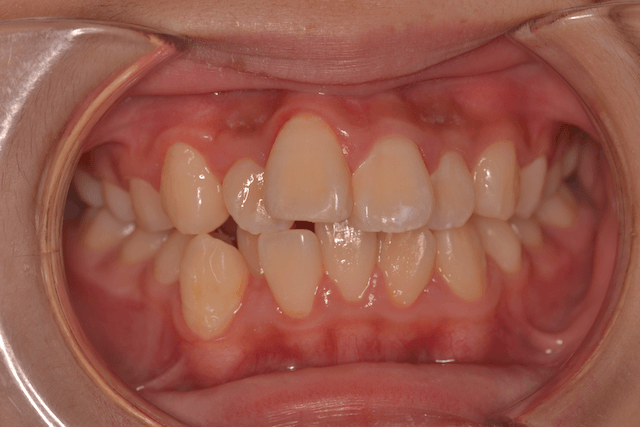

叢生を抜歯とDBSで改善した症例

※DBSとはダイレクトボンディングシステムと呼ばれており、ブラケットにワイヤーを通して歯を動かしていく矯正治療です。

患者情報

17歳女性

主訴

歯並びがガタガタ

行った治療内容

上下顎両側4番抜歯、DBS

治療のリスク

歯肉退縮、歯根吸収

治療期間

動的治療期間3年6か月

※ クリックして拡大することができます。